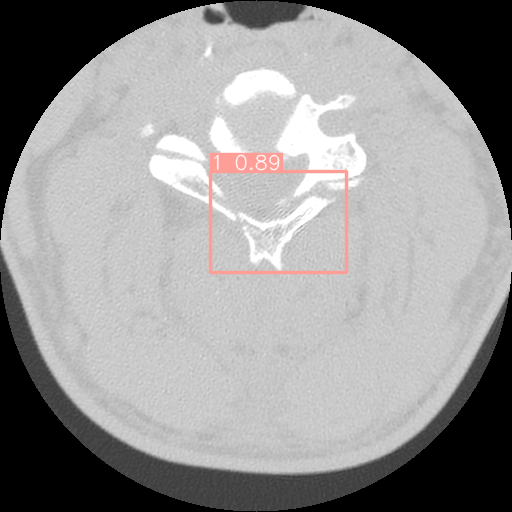

2.6 Fracture Detection

The dataset used in this study comprises bounding boxes representing the locations of fractures on vertebrae. To enrich the dataset, an additional set of around one thousand 2D images depicting non-fractured vertebrae has been integrated. The inclusion of these non-fractured samples aims to provide a more comprehensive and balanced representation of the data, facilitating improved model training.

In the pursuit of effective fracture detection, this study leverages the capabilities of two object detection algorithms: YOLOv5 and YOLOv8. These algorithms are to identify fracture occurrences within the images. The choice of utilizing YOLOv5 and YOLOv8 is grounded in their proven effectiveness in object detection tasks, making them suitable candidates for the fracture detection objective at hand.

For the cervical vertebrae fracture detection, the models are trained 100 epochs and the results are demonstrated in Table 3.

For fracture detection based on the results, it is clear that the performance of YOLOv8 outperforms YOLOv5. This is a significant improvement, especially considering that YOLOv8 is also faster than YOLOv5. Furthermore, although YOLOv8m has more parameters the mAP50 for YOLOV8s is a bit higher. On the other hand, YOLOv8m has higher mAP50-95. It is evident that YOLOv8s has demonstrated a strong ability to correctly classify images as “Normal" with 194 true positives and only 6 false negatives as presented in Figure 9.

However, it tends to make more errors when classifying images as “Fracture," as indicated by 97 false positives and 1347 true positives. This can be attributed to the nature of medical image analysis, where the cost of missing a “Fracture" (false negatives) may be considerably higher than misclassifying a “Normal" image as a “Fracture" (false positives). YOLOv8m, on the other hand, demonstrates a similar trend but with slightly improved performance when compared to YOLOv8s. It correctly classifies 192 “Normal" images and 1353 “Fracture" images. However, it still makes some errors, with 8 false negatives for “Normal" and 91 false positives for “Fracture". This model appears to strike a better balance between precision and recall for both classes, indicating a more robust classification performance.